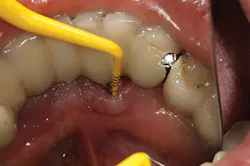

Treatment of peri-implant mucositis can often be accomplished via nonsurgical mechanical therapy. Although systemic antibiotics have been shown to reduce inflammation associated with peri-implant gingival tissue, as a monotherapy, they have been shown to be ineffective due to the bacterial recolonization of the implant surface without mechanical debridement.(12) Studies show that proper scaling and root planing with attention to bacterial plaque removal can be effective in reducing peri-implant mucositis lesions.(13) Localized drug delivery has also shown to have a positive effect in reducing mucositis lesions in conjunction with mechanical debridement (Fig. 2), especially in the areas of the mouth that are hard to reach.(14) After nonsurgical intervention, the patient should be recalled within three weeks. If no resolution of the inflammation has occurred, surgical intervention should occur.(15)